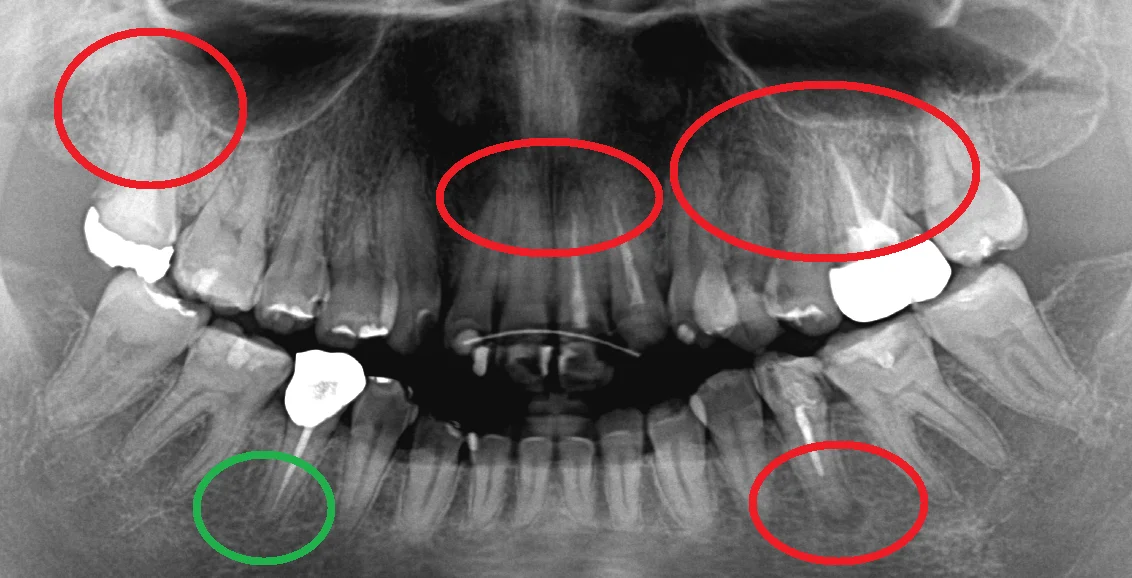

では本題の写真がこちらです。

こちらが術前で

赤丸の部分がすべて私の方で神経の治療を行わせていただいた部分になります。

緑丸の部分が治療を行っていないところですね。

そしてそれら全てで根の先の膿が小さくなっているのがわかります。

本数的に言うと・・・7本ですね。

また治療後の補綴物も全て適合よく入っているので、まったく問題ありません。